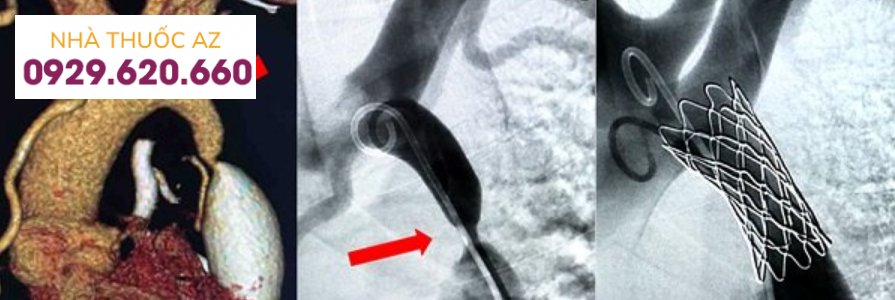

Hình ảnh trước và sau nong hẹp eo động mạch chủ